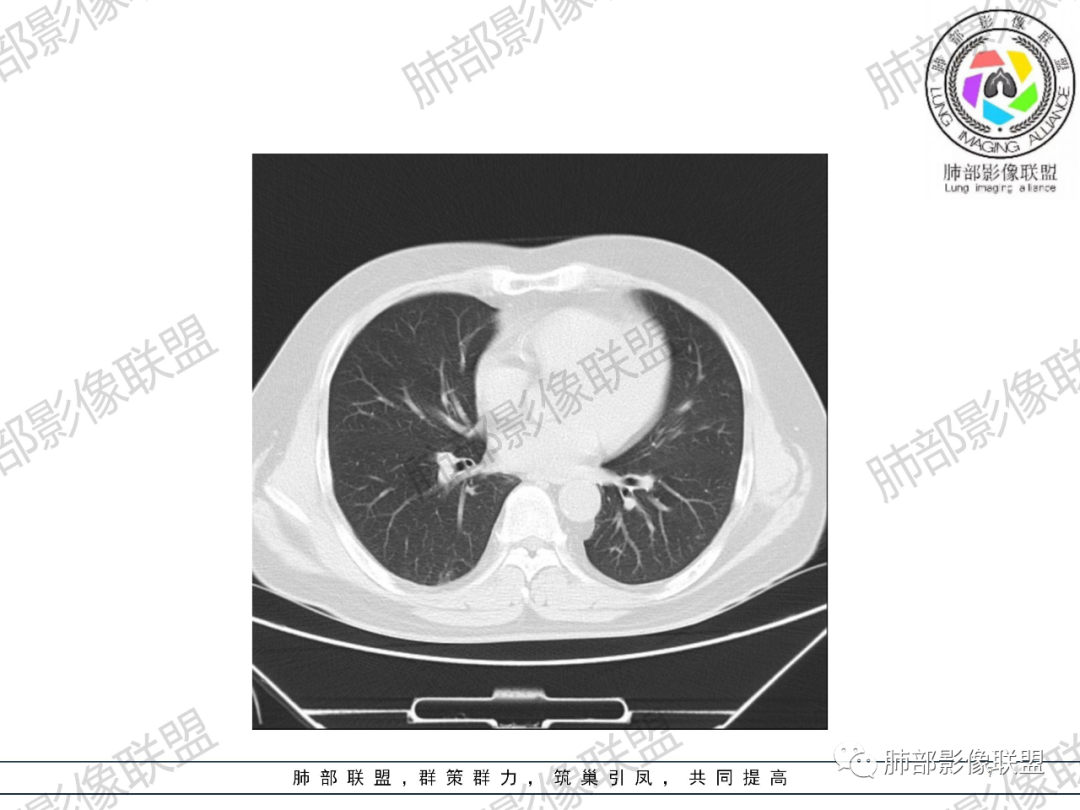

3.双肺散在微小结节影。